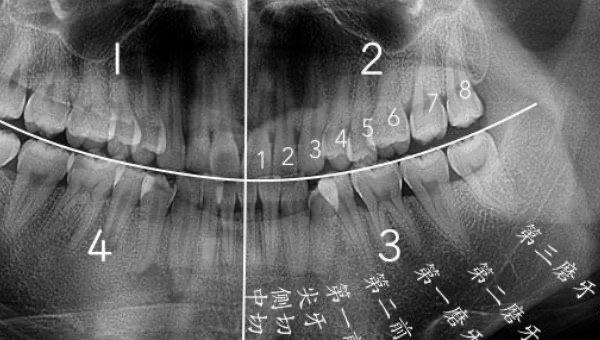

智齿是人类口腔内牙槽骨上最里面的第三颗磨牙,由于它经常会产生疼痛感,很多人选择将其拔掉,但部分人表示拔智齿后悔死了,那么这是为什么呢?快和小编去看看吧。

之所以会有人说拔智齿后悔死了,是因为他们在拔完之后没有注意口腔卫生的保持,导致伤口发现并肿胀,为自己带来了巨大的痛苦;有些人则是因为没有选择正规的口腔机构,医生不专业或消毒不彻底而引发感染。在拔完智齿后,还可能出现面部塌陷的情况,对个人形象产生影响。

人在成年之后一般都会长智齿,在其生长期间可能会出现牙龈肿痛的情况,严重影响人们的日常生活,所以很多医生都建议将其拔掉,但总有人会因为拔掉后出现的不良反应而后悔。事实上,智齿对人的危害没有那么大,如果其生长状态比较良好,则没有强行拔除的必要,除非是畸形智齿。

拔智齿会产生一定的后遗症,当这颗牙齿被拔掉之后,牙齿间的缝隙会变大,由此就会导致食物残留在缝隙中,形成牙石后会直接引起牙龈问题。此外,智齿拔掉后,该位置的牙槽骨也会被吸收掉,让前面的牙齿变得松动,然后引发牙周炎,如果不及时治疗,就会诱发不良并发症。

拔掉智齿后,患者需要紧咬棉花团并保持半小时以上,起到压迫止血的作用;拔牙后2小时内禁止饮食,24小时内避免漱口刷牙;患者在2-3天内少进行剧烈运动,同时减少伤口的触碰;日常饮食以偏软、偏凉的食物为主,禁止吸烟饮酒;拔牙当日切勿反复吸吮或吞咽口水。